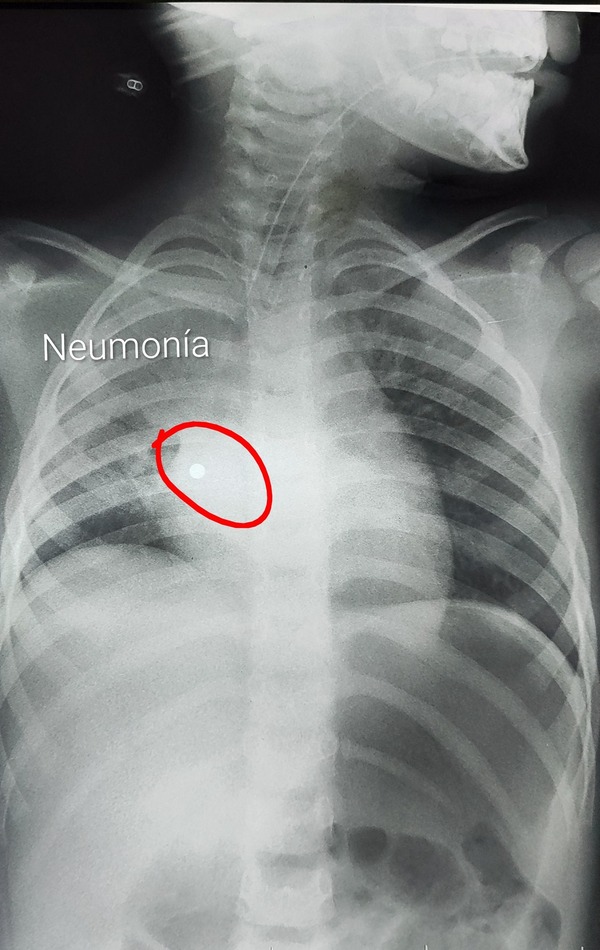

Niña de 4 años tragó un collar de perlas y sufre grave neumonía | Unicanal

Una niña de 4 años se encuentra en terapia intensiva luego de tragar un collar de perlas de metal. Uno de los accesorios terminó en el pulmón, lo que le produjo una grave neumonía. ...[Leer más]